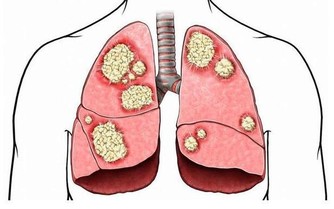

8 、咳嗽不止。

美國喬治城大學醫學院拉尼特·米歇里博士表示,

如果莫名其妙的咳嗽持續不斷,超過3—4周,就應該及時看醫生,有可能是肺癌或喉癌的徵兆。

比如,長期腹痛是大腸癌的症狀,胸部疼痛可能是肺癌引起的,骨頭酸痛則可能是癌症轉移的症狀。